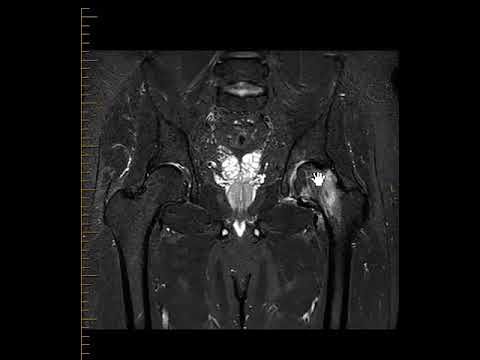

Osteonecrosis of the Hip (femoral head) - Avascular Necrosis

Avascular Necrosis of the Femoral Head #hippain #trauma #radiology

AVASCULAR NECROSIS OF FEMORAL HEAD || DR SANJAY DESAI || #mriteachingcourse

Bandi Babita "STUDY OF STAGING OF MAGNETIC RESONANCE IMAGING INAVASCULAR NECROSIS OF FEMORAL HEAD"